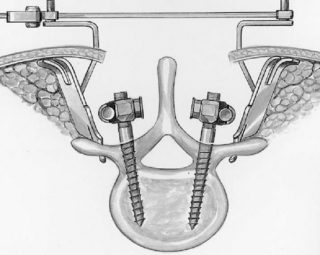

К хирургическому лечению прибегают, если консервативная терапия не помогает восстановить здоровье позвоночника. В таком случае практикуют встраивание в столб пластин из металла, которые соединяют смежные позвонки. Деформированные костные структуры при этом удаляют.

Хирургическое вмешательство позволяет зафиксировать позвоночник в шейном отделе, ограничив его подвижность. Несмотря на терапевтическую ценность метода, он имеет много рисков. После операции требуется соблюдение восстановительных мер не менее года.

Проводится операция: с помощью штифтов врач фиксирует правильное положение позвонков. Прибегают к хирургическим манипуляциям в редких случаях, из-за того, что восстановительный процесс после проведения операции длительный. Не исключены осложнения.